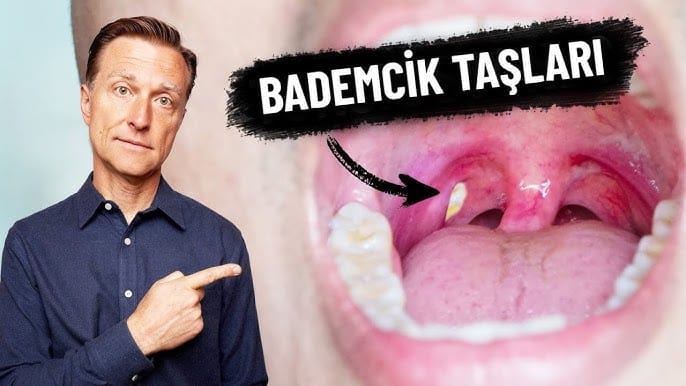

Bademcik taşları önlenebilir mi?

Bademcik taşlarını önlemek zordur çünkü bunlar ağızdan mideye geçen yiyecek ve diğer maddelerle oluşur. Bunları önleyemeseniz de, iyi bir ağız hijyeniyle bademcik taşlarının oluşumunu en aza indirebilirsiniz.

Yemeklerden sonra, sabahları ve yatmadan önce dişlerinizi fırçalayın . Dişlerinizi fırçalarken dilinizi de nazikçe fırçalayın ve ardından diş ipi kullanın. Alkol bazlı olmayan bir gargarayı düzenli olarak kullanın. İyi bir ağız hijyeni, bademcik taşı oluşumuna yol açabilen ağzınızdaki bakterileri azaltır.

Bademcik taşları sağlığınız için zararlı değildir ve bir sorun olmaktan çok, can sıkıcı bir durumdur. Bademcik taşları hakkında sık karşılaşılan bir şikayet, bademciklerde biriken bakteriler nedeniyle ağız kokusuna neden olmalarıdır.